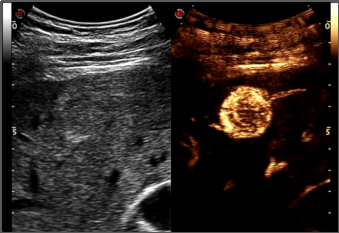

造影谐波成像Ultra-CnTI

通过对发射脉冲频带及能量的精确控制,使脉冲最佳的匹配造影剂微泡的非线性响应,从而获得纯净、丰富的、超强的造影剂回波信号:HFRI 高帧频动脉关注成像-更好的造影动脉相CCPI编码造影成像-利用编码成像原理进行发射和接,提高深部组织的造影穿透力DCTI造影三频段接收技术-提高造影剂检测灵敏度,更少的造影剂用量DP声压精控技术-可最大限度的保护微泡,减少微泡破裂,保证持续的、清晰的造影剂灌注观测,可进一步提高对造影微泡敏感的检测,具有更好的造影延迟相全身应用,尤其高频造影更为显著-腹部、高频、心脏、腔内、术中探头均支持造影功能,具有造影双幅动态显示和一键转换调节功能,造影动态图像连续长时间不间断采集;

术前诊断

术后评估